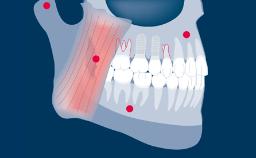

Complete dentures have a longstanding record for rehabilitation of edentulous jaws, but are frequently associated with problems of retention and stability. Patients with these issues may be referred for implant therapy often without first addressing problems of inadequate design and fit of the complete prostheses.

Improving the design and construction of the prostheses may alleviate problems of retention and stability without the need for implants. Therefore, the first step in the rehabilitation of edentulous arches is to establish whether or not the prostheses are adequate.

A complete denture is defined as a removable dental prosthesis that replaces the entire dentition and associated structures of the maxilla or mandible. Complete removable dentures must be designed as ideally as possible.